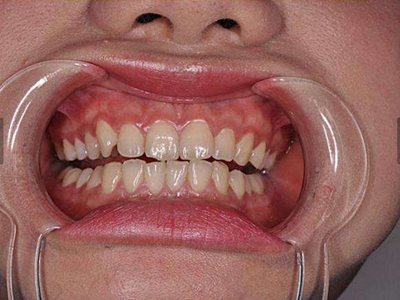

慢性龈炎又称边缘性龈炎或单纯性龈炎,主要表现为游离龈和龈乳头因炎性水肿,而变为鲜红或暗红色,龈缘变厚,龈乳头圆钝肥大。慢性龈炎的患病率高,治愈后仍可复发,部分患者可发展成为牙周炎。

慢性龈炎的病损部位一般局限于游离龈和龈乳头,以前牙区为主,尤其以下前牙区最为显著,患者常因刷牙或咬硬物时牙龈出血而就诊。游离龈和龈乳头颜色变为鲜红或暗红色,病变较重时炎性充血可波及附着龈。龈缘变厚,龈乳头圆钝肥大,可增生呈球状,覆盖牙面。牙龈松软脆弱,缺乏弹性。